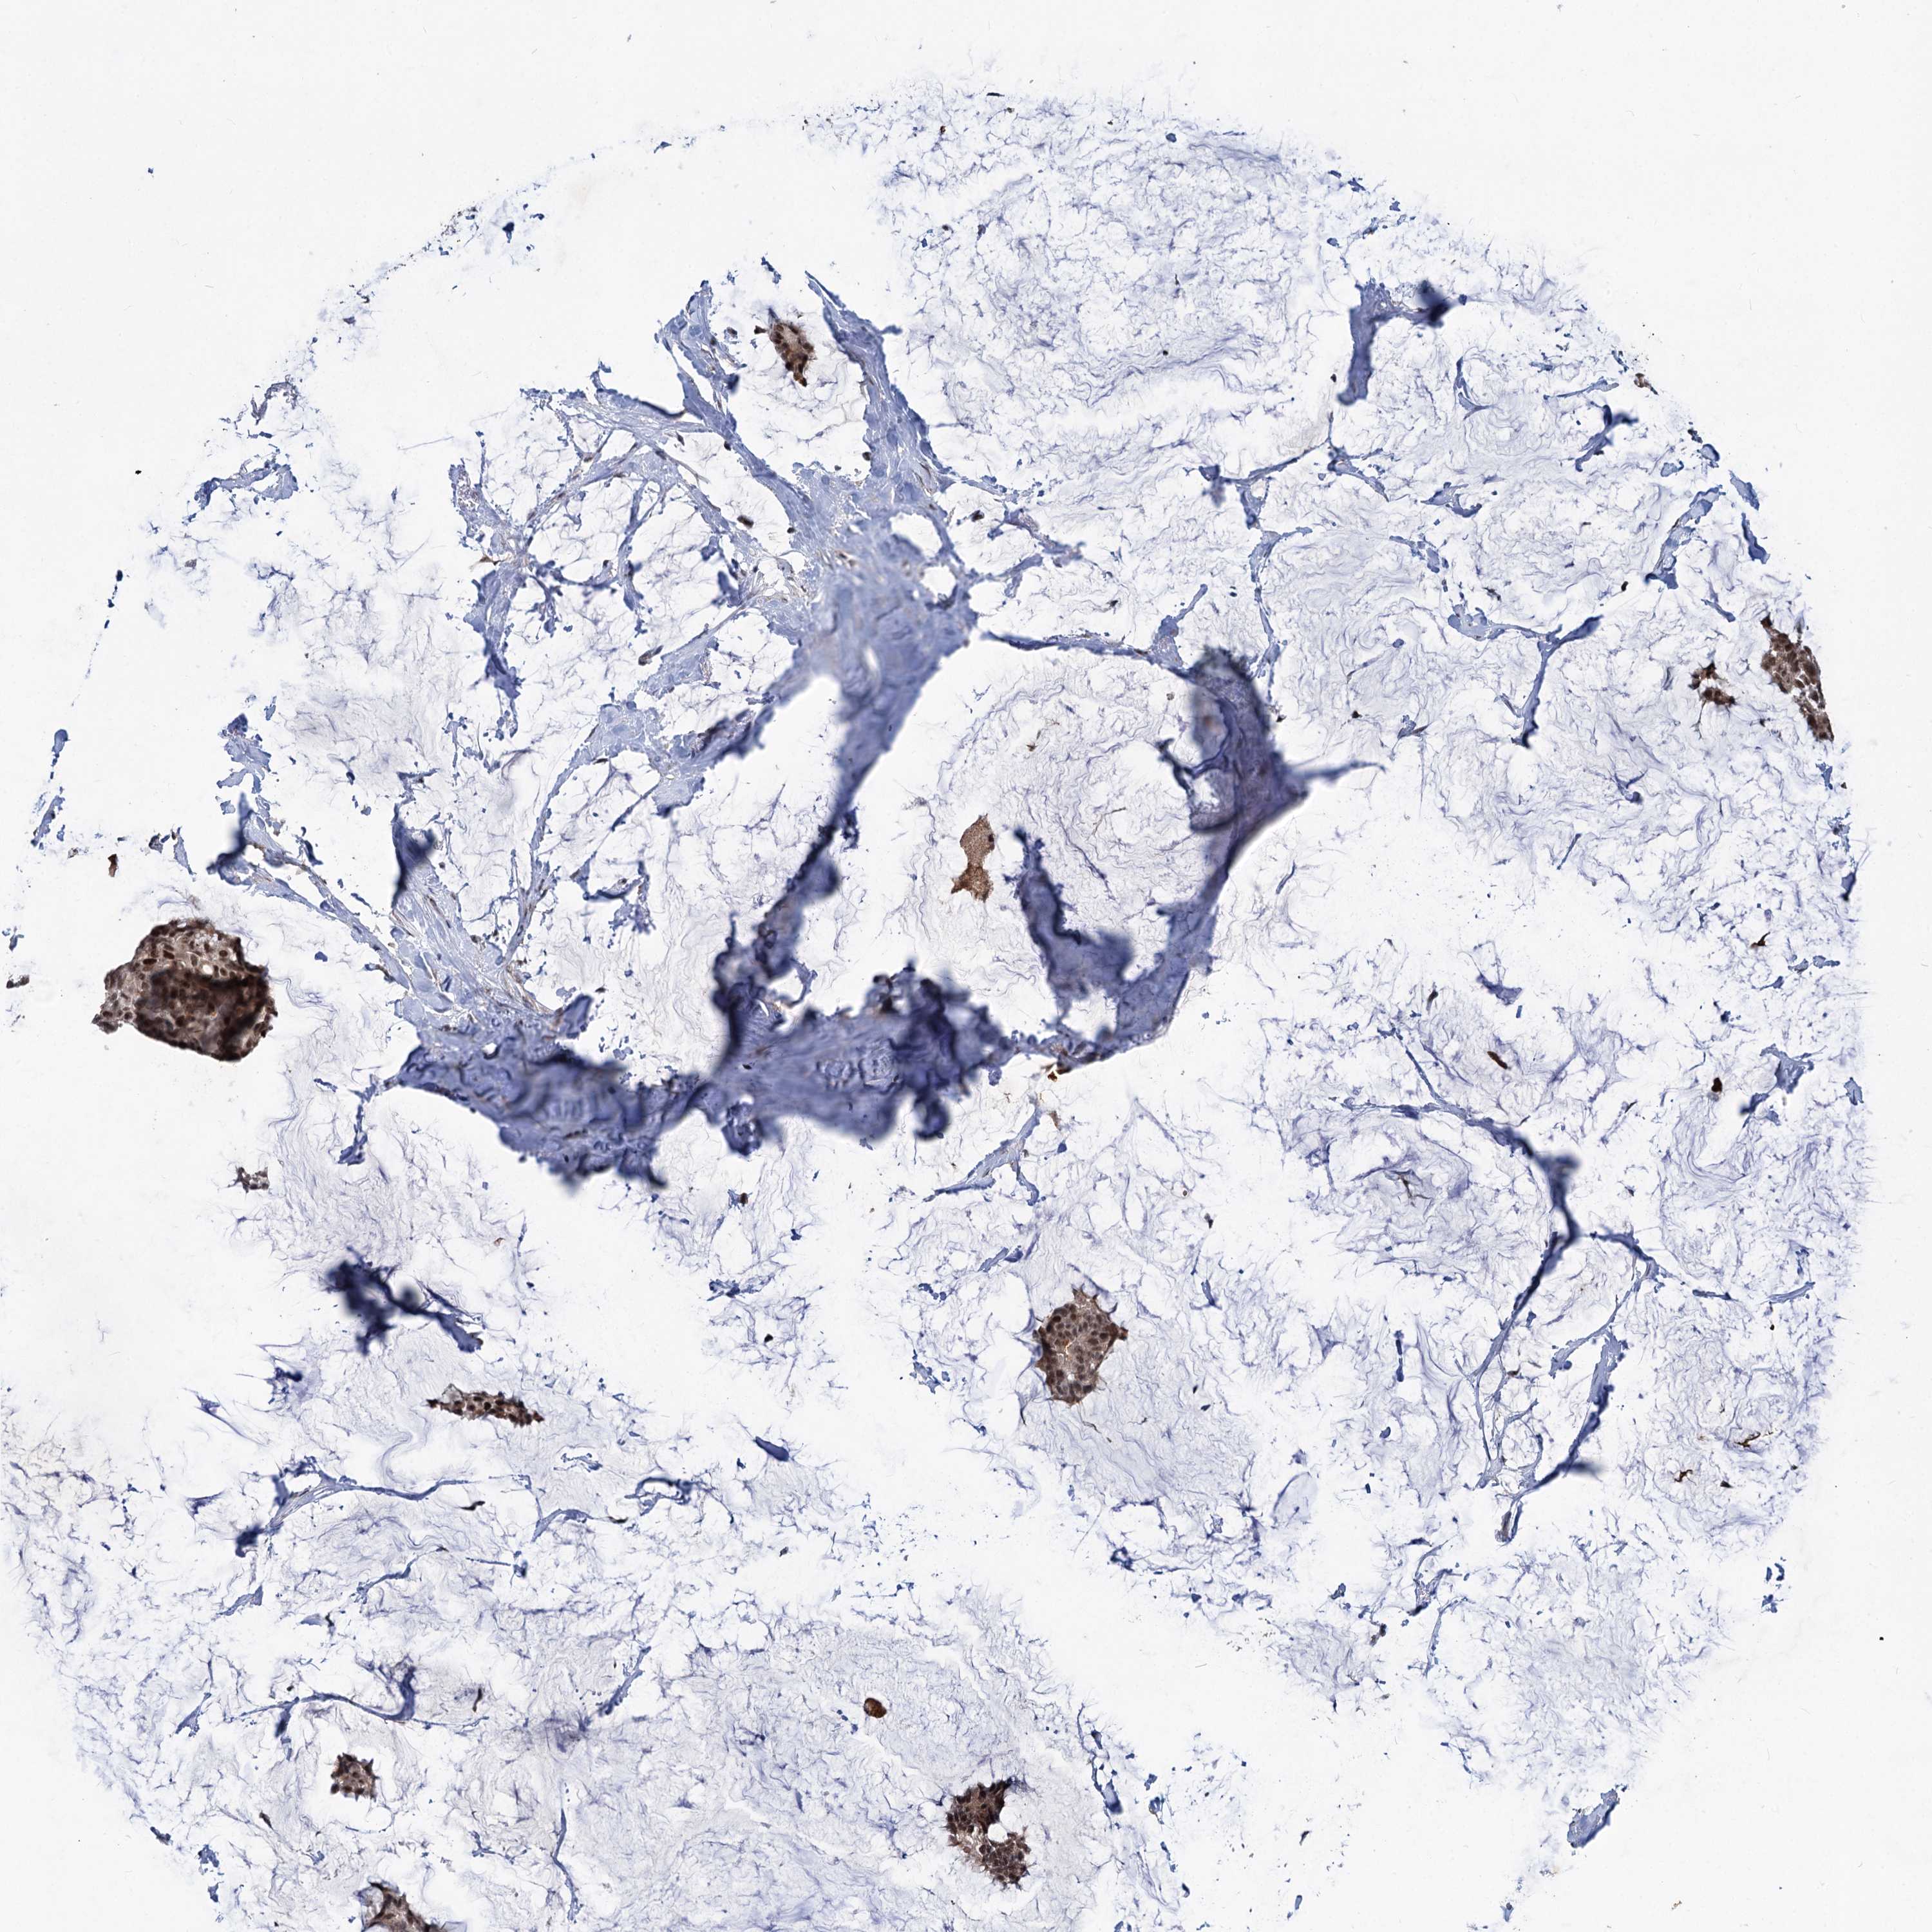

CANCER BREAST CANCER Show tissue menu

BRCA TCGA BRCA VALIDATION PROTEIN EXPRESSION